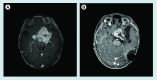

Figure 2.

Figure 2.. Bilateral optic nerve glioma in a 2-year-old child with neurofibromatosis type 1.

Figure 3.

Figure 3.. Response to single-agent vinblastine in a child with pilomyxoid astrocytoma.

(A) At the time of diagnosis, aged 12 months and (B) at end of chemotherapy, 18 months later.